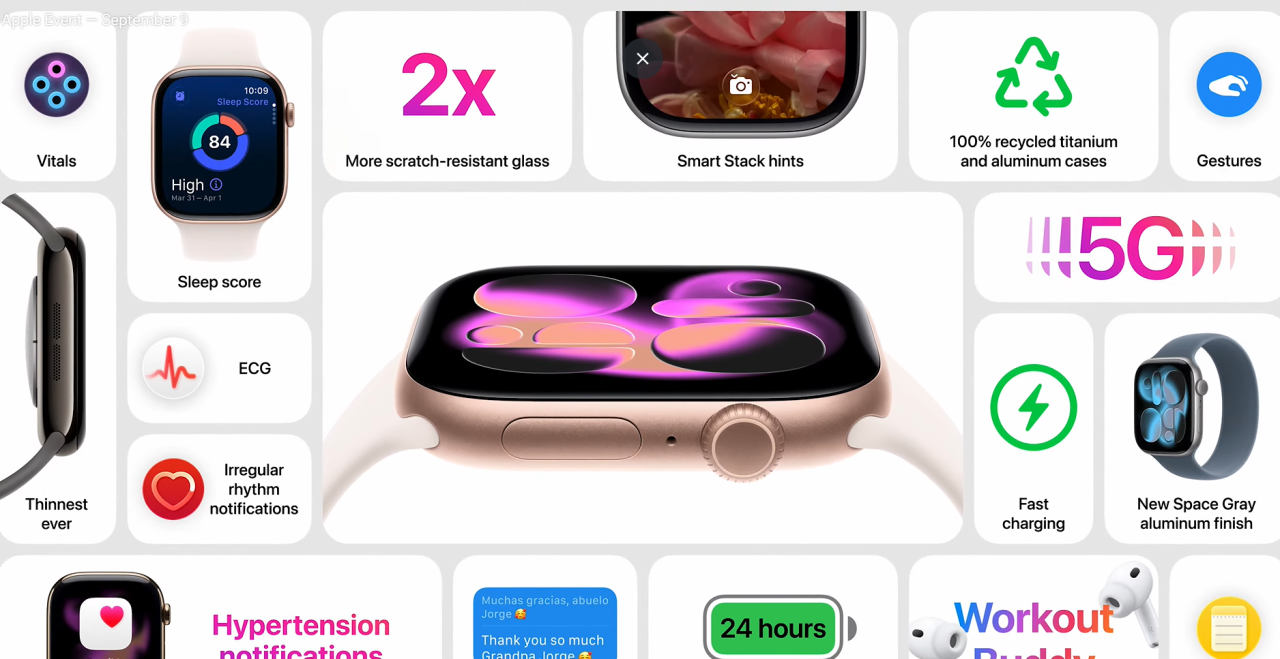

Apple Watch Series 11

Apple представила нове покоління розумних годинників, які стали найтоншими і найлегшими за всю історію бренду. Корпус отримав збільшену стійкість до подряпин – удвічі вищу порівняно з Series 10, а новий чип S11 забезпечує роботу всіх AI-функцій watchOS 26, включно з поліпшеним опрацюванням даних про здоров’я та активність.

У годинник додали нові функції для здоров’я: виявлення гіпертонії та оцінка сну Sleep Score на основі фаз сну, регулярності відходу до сну і тривалості пробуджень.

Крім того, Series 11 тепер підтримує 5G-мережі через технологію RedCap, що прискорює передачу даних і дає змогу залишатися на зв’язку навіть у віддалених місцях.